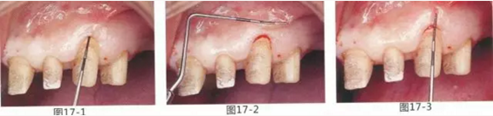

圖17-1~3 左上3的牙周袋探測值為3mm,角化牙齦寬度為2mm。也就是完全不存在附著齦,如果這種狀態(tài)下佩戴修復體的話,很有可能發(fā)生頸部暴露等問題。

圖17-4 左上1,2進行齦瓣根尖側轉移,左上3,4進行游離牙齦移植,在去除牙周袋的同時獲取附著齦。

圖17-5 牙周治療完成后的正面照。左上3,4部位處游離齦移植片的上端通過骨膜縫合固定在頰側嵴頂部。這樣可以使其愈合效果與齦瓣根尖側轉移相同。